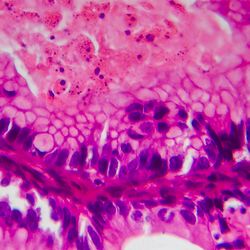

Gynaecological Cancers

The Gynaecological Cancers Group studies the epidemiology of gynaecological cancers, particularly ovarian and endometrial cancers, from aetiology to diagnosis, patterns of care, quality of life and survival.